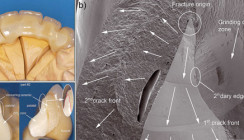

Zähne mit vertikalen Frakturen gelten gemeinhin als verloren. Meistens sind es devitale Seitenzähne, und oft sind die Patienten an deren Erhaltung hoch interessiert. Der Autor machte vor zwölf Jahren erste Versuche der Restauration. Daraus ergab sich allmählich die folgende Einteilung der vertikalen Frakturen mit ihren je weiligen Aufbauten (Abb. 1) und Prognosen: Laterale Frakturen verlaufen schräg zur Seite. Der Bruch endet meist nahe über oder unter dem bukkalen Alveolarrand. Das kleinere Fragment ist beweglich und schmerzt bei Belastung. Prognose gut.

Zentrale Frakturen spalten den Zahn genau zwischen den Wurzeln. Beide Zahnhälften sind fest. Prognose bedingt gut. Apikale Frakturen teilen eine Wurzel längs des Wurzelkanals von mesial nach distal bis zum Apex. Beide Zahnhälften sind fest. Prognose noch unsicher. Erfolge ergeben sich nur, wenn beim Präparieren keine Blutung entsteht, wenn die verbleibenden Fragmente fest sind und wenn sie genug Platz für Retentionen haben. Die fertigen Aufbauten sind jeweils sofort wieder schmerzfrei belastbar. Bei spiralförmig oder transversal verlaufenden Wurzelfrakturen gelang bisher noch keine Restauration.

Laterale Frakturen (Abb. 2a)

Ausschlaggebend für das Gelingen ist die blutungsfreie Präparation. Das lose Fragment wird deshalb schon zu Beginn der Sitzung mit dem Desmotom entfernt (Abb. 2b). Die Blutung stoppt dann von selbst während der Behandlung.

Zentrale Frakturen (Abb. 4)

Apikale Frakturen (Abb. 5a)

Ausschlaggebend ist die Säuberung des Bruchspalts im Wurzelkanal. Spalt im Wurzelkanal Die Wurzelfüllung wird mit einem großen Rosenbohrer bis in eine Tiefe von etwa 15 mm entfernt. Die apikalen 2–3 mm werden mit Wurzelkanalfeilen gesäubert. Darauf wird mit einem kleinen Rosenbohrer der Frakturspalt so gut als möglich exkaviert. Nun kann der Mikro-Applikator den erwei terten Kanal mit Primer, Adhäsiv und Versiegler erreichen. Zur Füllung wird zunächst fließfähiges Komposit tropfenweise einlentuliert und gehärtet (Abb. 5c). Danach wird transparentes Komposit in kleinen Portionen und mit langen Härtezeiten in den Kanal eingebracht.